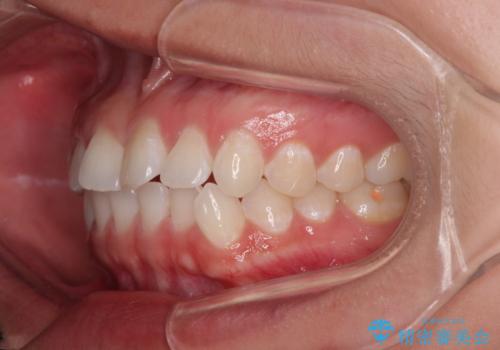

- 上下前歯のデコボコを気にして来院された患者様です。

ワイヤー矯正でもマウスピース矯正でも可能でしたが、短期間で、自身の手を煩わせることなく治療を行いたいとのことで、ワイヤー装置にて矯正治療を行うこととしました。

僅か半年強、あっという間に治療を終えることができました。